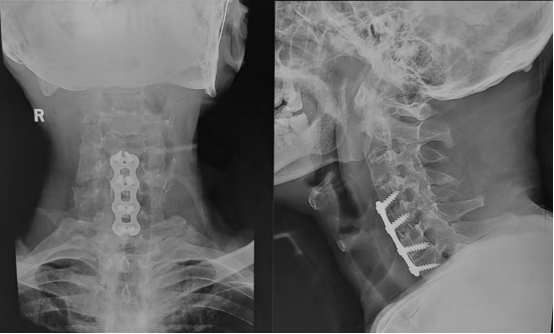

经过1个半小时精心施术,随着最后一道缝合完成,手术宣告成功。手术室里紧张凝重的气氛,终于得以缓解。术后X光片显示,内固定位置准确,颈椎序列得到理想恢复。

术后脊柱序列完全恢复

返回普通病房后,在护理团队悉心照料下,术后第一天,该患者顺利拔除引流管,开始自行下地活动,神经功能评估显示已完全恢复,四肢活动自如,之前麻木无力感明显改善。